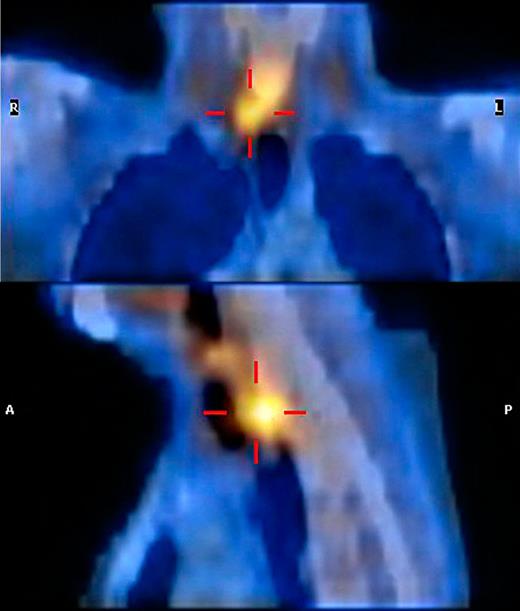

A 79-year-old woman presented at the emergency department with pain during swallowing. Her past medical history included atrial fibrillation for which she had been receiving oral anticoagulants (Acenocoumarol). Three weeks earlier during routine laboratory investigation, an elevated serum calcium level was found. Urinary calcium excretion was 312 mg/24 h, ruling out familial hypocalciuric hypercalcemia. Further investigation with ultrasound, scintigraphy and SPECT scan had revealed a right-sided enlarged parathyroid gland (Fig. 1). Calcimimetic therapy [Cinacalcet (Mimpara®) 30 mg twice daily] had been initiated and surgical extirpation was scheduled.

SPECT scan demonstrating a right-sided parathyroid gland adenoma.